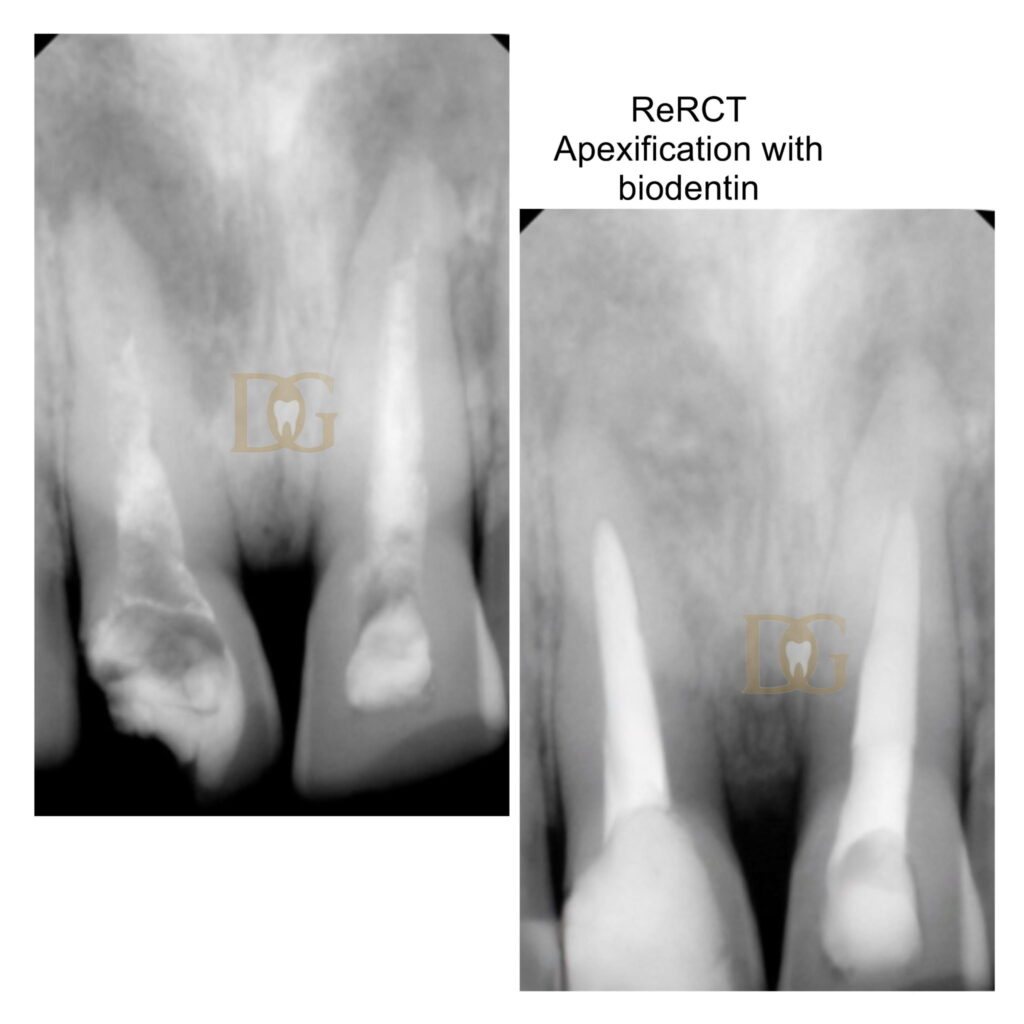

Her clinical expertise includes advanced root canal procedures such as single-visit and multi-visit RCTs, management of calcified and curved canals, retreatment of failed cases, and complex procedures like perforation repairs and third molar endodontics. She is also proficient in post and core restorations, along with aesthetic and restorative rehabilitation aimed at preserving natural dentition.

- Complex Retreatments